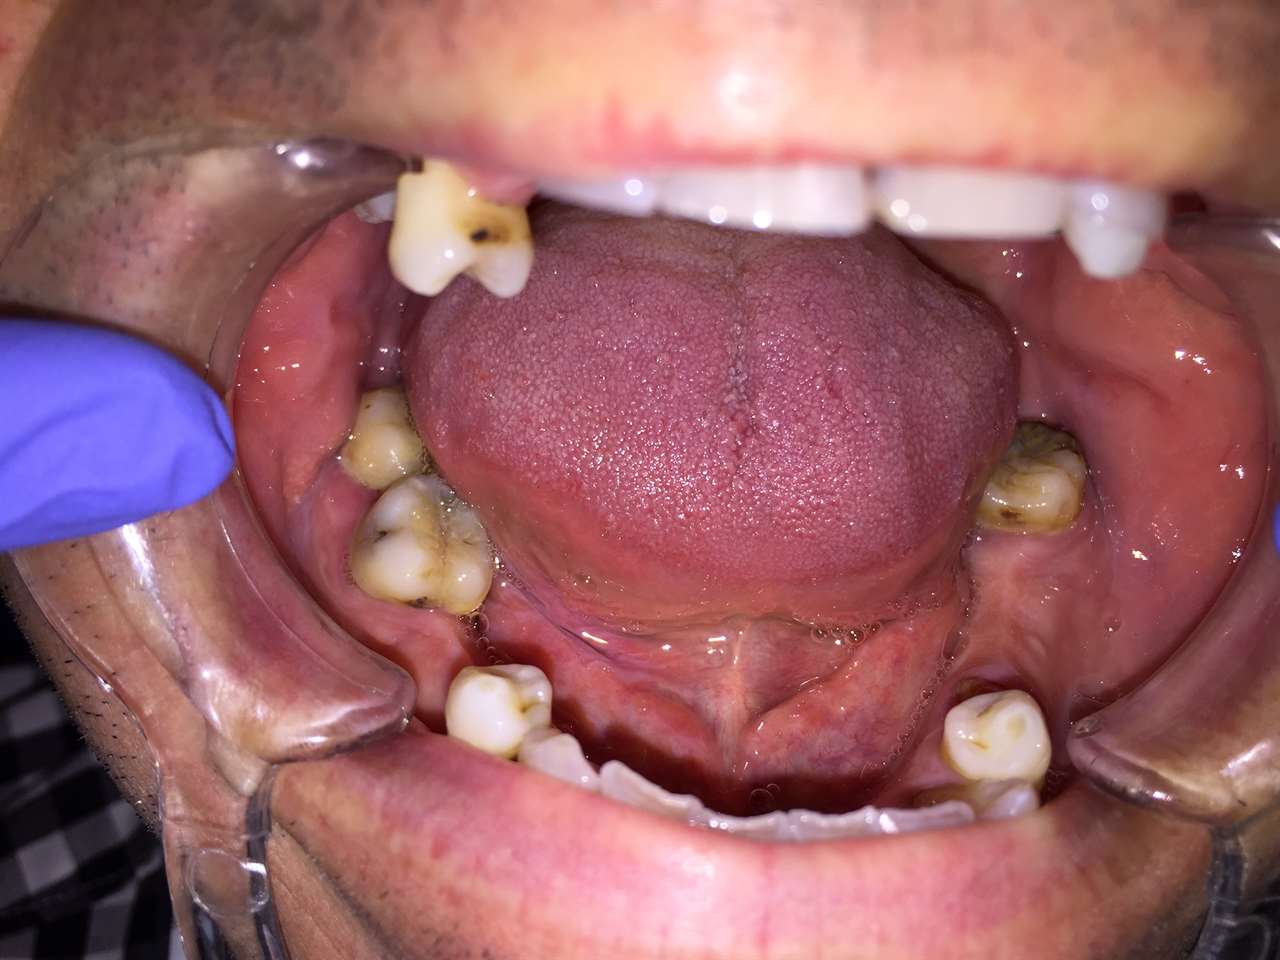

Alsó állcsont teljes rehabilitációja 72 óra alatt, azonnal terhelhető implantátumokkal súlyos paradontitisben szenvedő dohányzó páciens esetében. Az alsó állcsont fogai mind mozogtak az előrehaladott fogágypusztulás miatt.

A fogakat eltávolítottuk, a gyulladt, fertőzött csontot kitakarítottuk, kifertőtlenítettük, majd azonnal implantáltunk.

Svájci, IHDE márkájú, azonnal terhelhető implantátumokat helyzetünk be, és ezekre harmadnapra rögzített, hosszútávú, fémvázas, esztétikus műanyaggal leplezett hidat ragasztottunk be.

Ezt az ideiglenes hidat a sebek gyógyulása miatt használjuk, de tartóssága miatt véglegesként is használható. A legtöbb esetben, ahogy itt is, 6 hónap múlva porcelán hídra cseréljük, a teljes gyógyulás után.